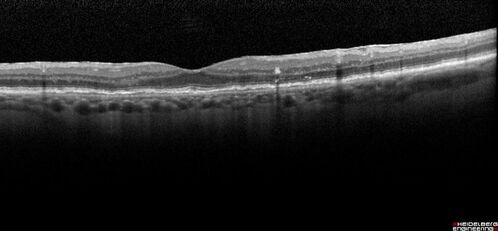

Pigment migration in dry age-related macular degeneration

80 year old female. Dry AMD with GA in the left eye and pigment migration visible on OCT scan.

VA 20/40 OD, 20/160 OS